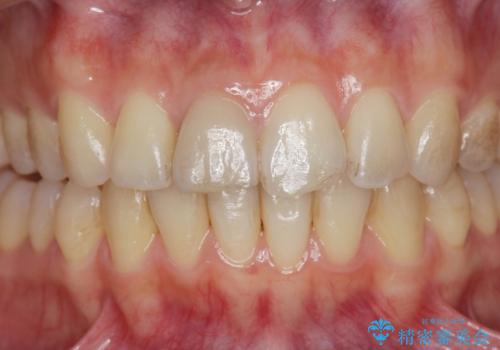

自然な色調をセラミッククラウンで再現することができ、審美性の改善に大変喜んでいただくことができました。